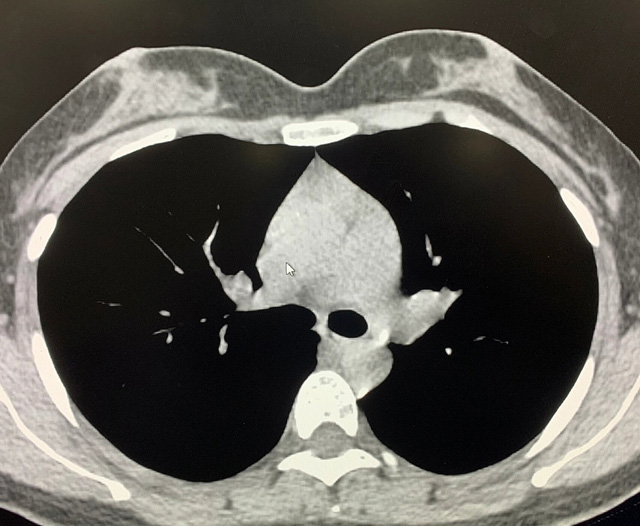

能譜純化技術(shù)的核心是通過物理濾過(如錫濾片)或軟件算法,選擇性濾除低能X射線光子,保留高能光子。在胸部低劑量CT掃描中顯著提升了圖像質(zhì)量與輻射劑量的平衡。

優(yōu)勢輻射劑量顯著降低相較于常規(guī)CT,輻射劑量減少約70%-90%,尤其適合需多次隨訪的高危人群(如肺癌篩查),降低輻射相關(guān)癌癥風(fēng)險(xiǎn)早期肺癌篩查效果明確可清晰檢測毫米級肺結(jié)節(jié),顯著提高早期肺癌檢出率,降低死亡率。檢查快捷且普及性高單次掃描僅需數(shù)秒,無需對比劑,設(shè)備廣泛配置于基層醫(yī)院,便于大規(guī)模篩查。長期成本效益顯著雖單次費(fèi)用與常規(guī)CT相近,但早期干預(yù)可大幅降低晚期治療費(fèi)用及社會(huì)醫(yī)療負(fù)擔(dān)。技術(shù)優(yōu)化提升圖像質(zhì)量迭代重建算法(如ASIR、MBIR)在降低劑量同時(shí)減少噪聲,平衡影像質(zhì)量與安全性。